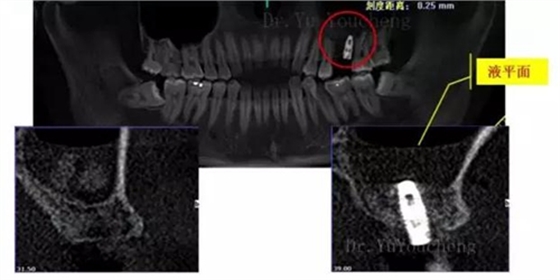

系列課開(kāi)播前小編為大家預(yù)告了一例上頜竇外提升術(shù)后種植體方向改變的病例,當(dāng)時(shí)頓生種種疑惑:“真的么?怎么會(huì)?怎么辦!!”在本次課程中余教授給出了答案:上頜竇外提升同期種植有一重要的因素,即種植體初期穩(wěn)定性的獲得。該患者由于其骨量的嚴(yán)重不足,雖然可通過(guò)大直徑覆蓋螺絲保證種植體不至于滑落,但隨著竇粘膜的運(yùn)動(dòng)和部分移植骨的吸收,種植體方向最終受到了影響,這也提示我們?cè)谥贫ㄖ委熡?jì)劃過(guò)程中應(yīng)慎重考慮這一因素,以確保更好的種植預(yù)后效果。